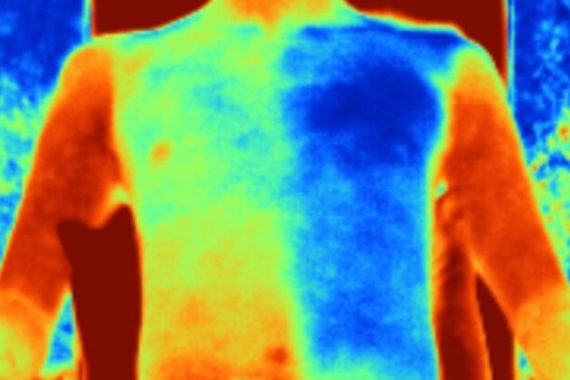

त्यानंतरच्या चाचण्यांत हे कापड आणि त्याचबरोबर नेहमीच्या वापरातली विविध प्रकारची कापडं, औष्णिकदृष्ट्या मानवी त्वचेशी साधर्म्य असणाऱ्या पृष्ठभागावर ठेवण्यात आली. मध्यान्हीच्या उन्हात ठेवल्यानंतरही या कापडाचं तापमान सुती कापडाच्या तुलनेत सुमारे पाच अंश सेल्सियसनं कमी तर, लिननच्या कापडाच्या तुलनेत ते सुमारे सहा अंश सेल्सियसनं कमी भरलं. हा प्रयोग प्रत्यक्ष एका स्वयंसेवकावरही करण्यात आला. या स्वयंसेवकाला एक जाकीट घालायला दिलं आणि त्याला मध्यान्हीच्या उन्हात बसवलं. या जाकिटाचा अर्धा भाग या ‘थंड’ कापडापासून बनवलेला होता आणि उर्वरित अर्धा भाग बाजारात मिळणाऱ्या सुती कापडापासून बनवला होता. या जाकिटाच्या आतील तापमानाचं मापन केलं गेलं. दोन्ही भागातल्या तापमानांत सुमारे पाच अंशांचा फरक होता!